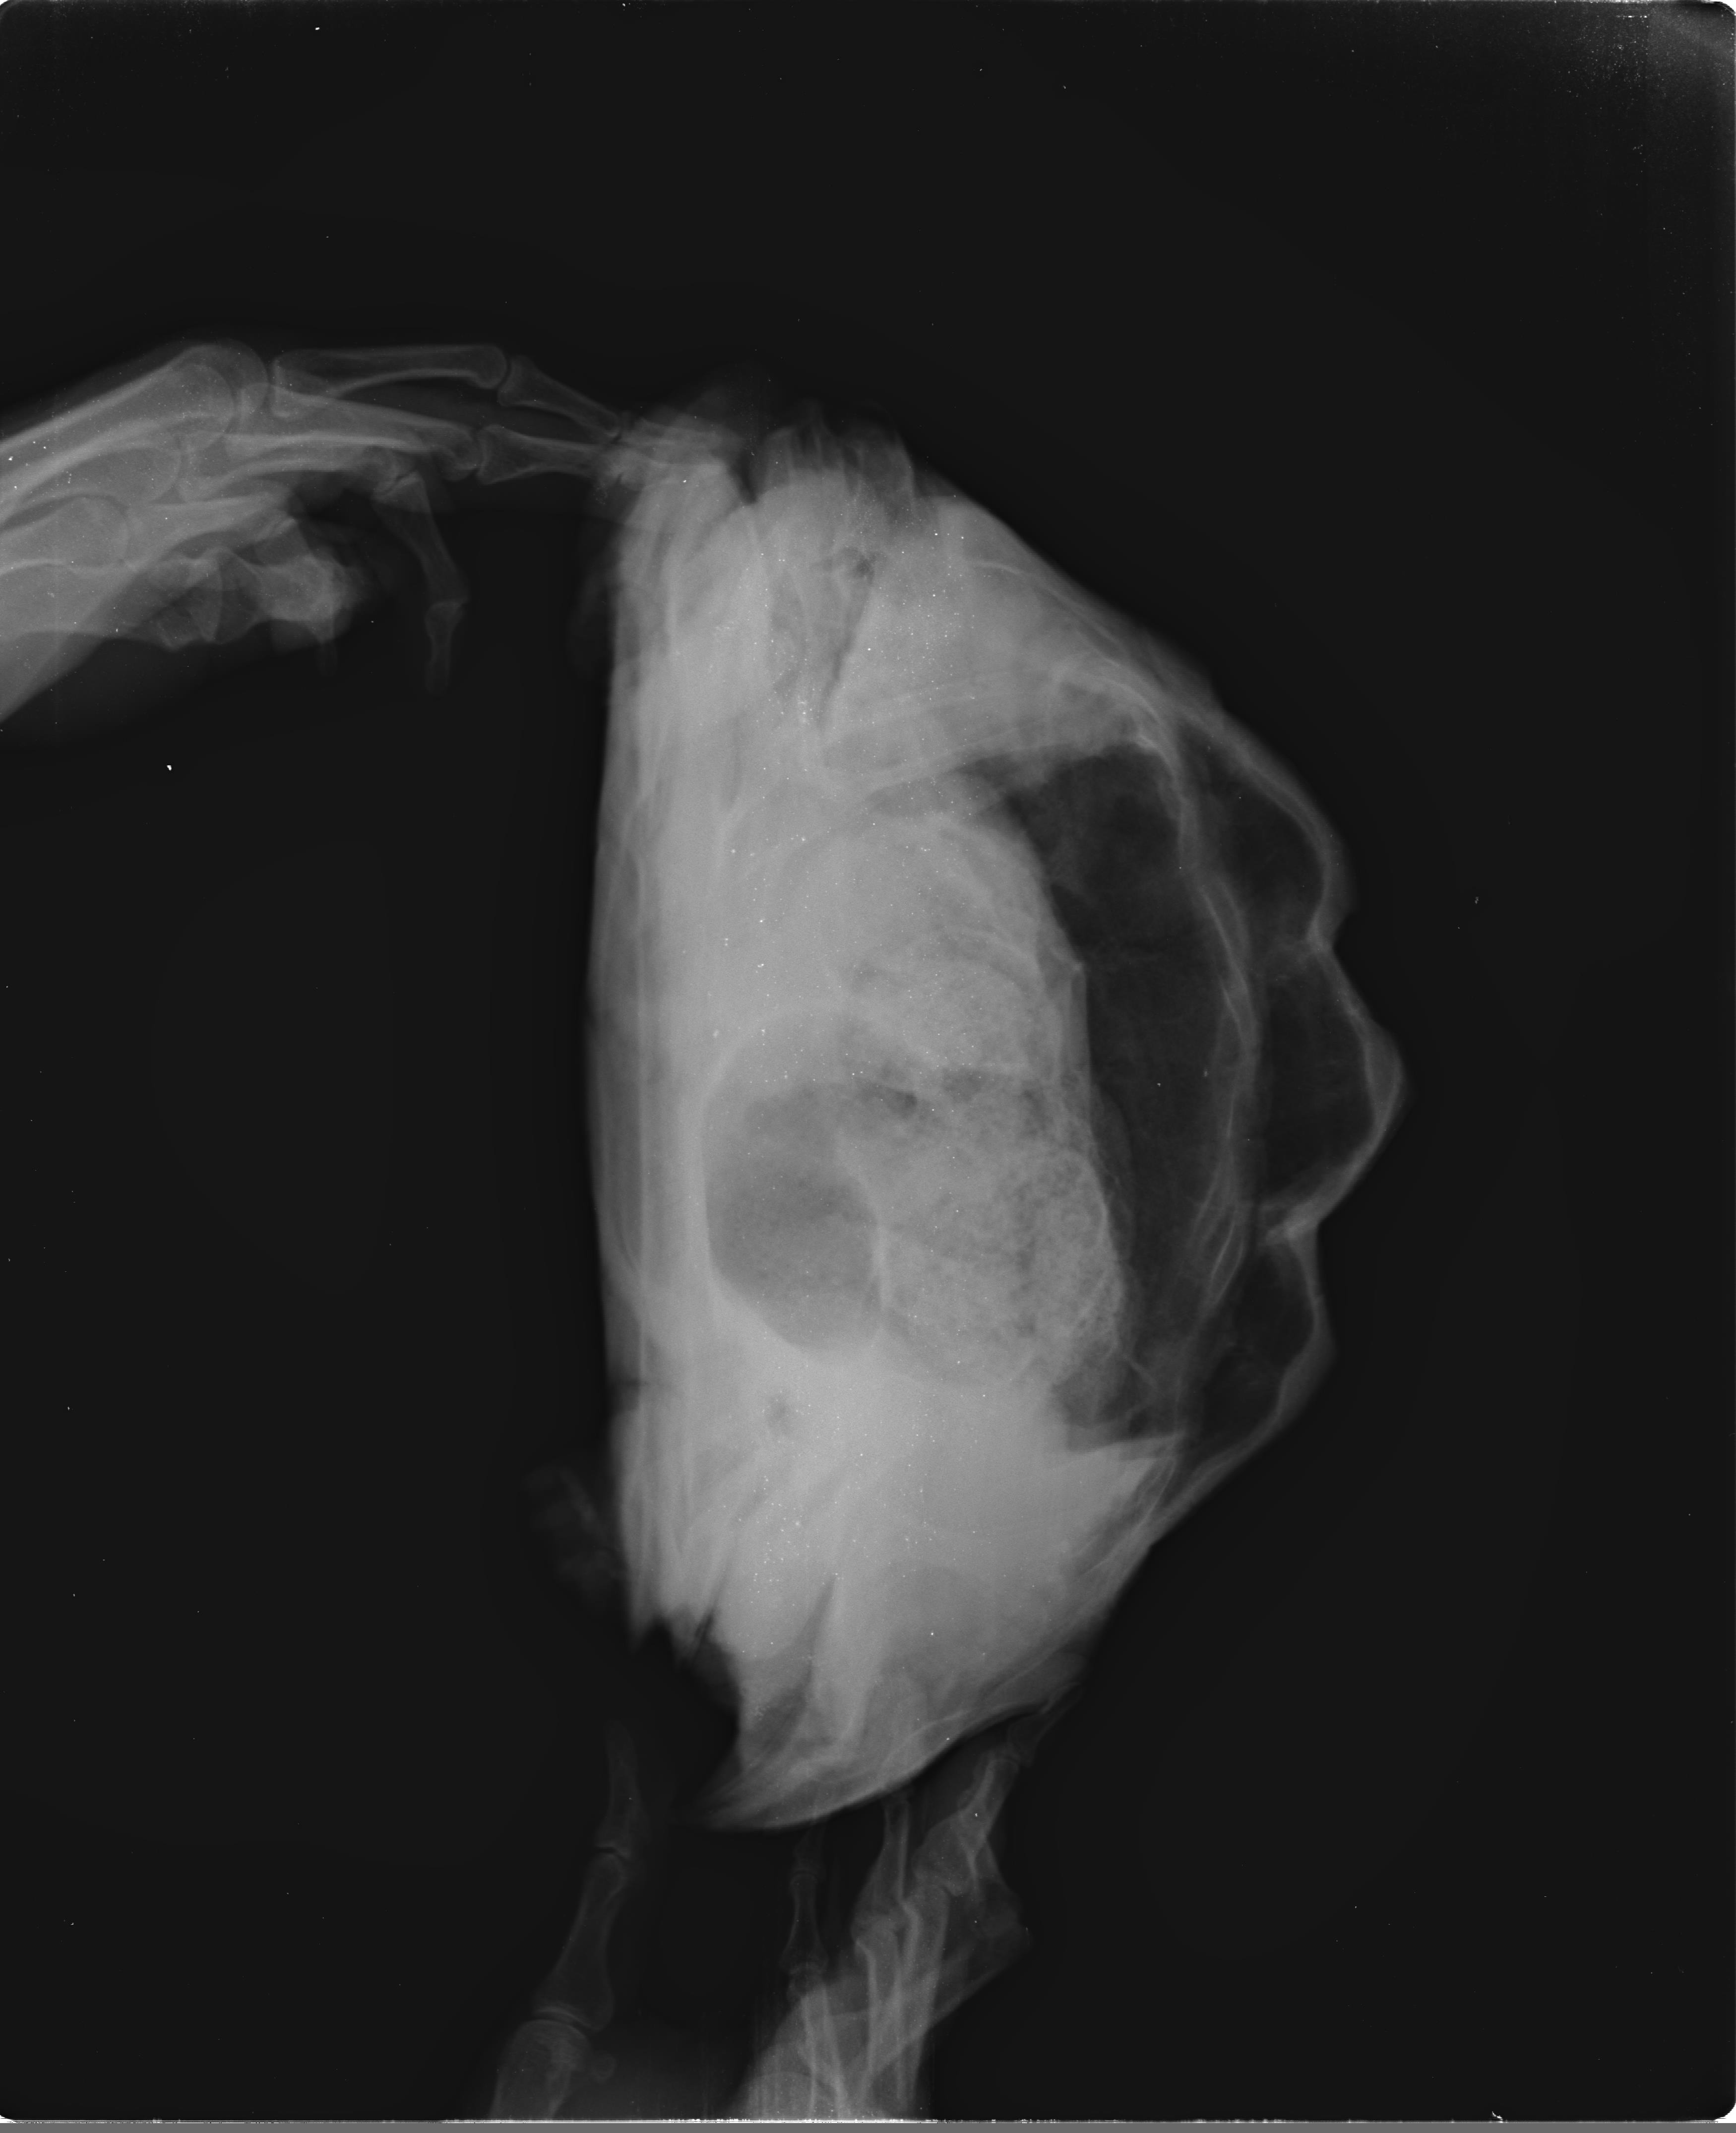

거북 X-Ray검사:정상(Normal)-레오파드거북 토르(11-08-2012, 2.6kg) 작성자가람캡틴|작성시간26.03.31|조회수2 목록 댓글 0 글자크기 작게가 글자크기 크게가 다음검색 현재 게시글 추가 기능 열기 북마크 공유하기 신고 센터로 신고 댓글 댓글 0 댓글쓰기 답글쓰기 댓글 리스트